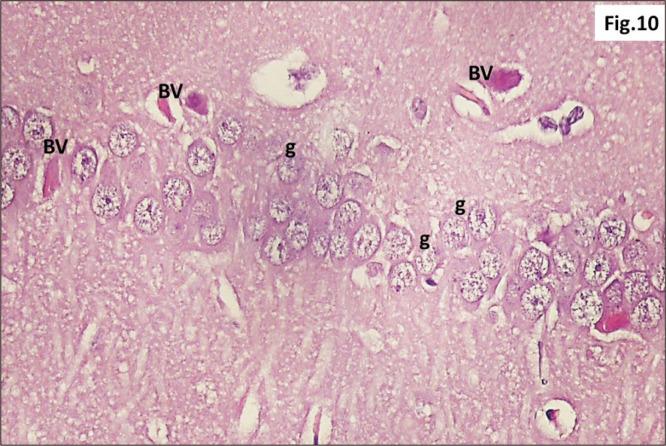

Energy drinks are available worldwide and frequently consumed to increase energy level and compensate lack of sleep. Energy drinks consumers aim to improve their cognitive functions. Red Bull is the most popular energy drink consumed in Egypt. However, the link between the impact of energy drinks on the structure of hippocampal cornu ammonis 1 (CA1) and dentate gyrus (DG), a highly vulnerable brain regions to various insults, has not yet documented. To study the effect of energy drinks on structure of hippocampal CA1 and DG of adult male albino rats. Twenty one adult male albino rats were divided into three groups; group I control group, groups II and III received Red Bull, with a dose of 3.75 ml/kg/day orally using gastric tube for four and eight consecutive weeks respectively. At the end of the experiment, brains were dissected and hippocampal specimens were processed for histopathological and immunohistochemical studies. Histopathological examination of hippocampal sections in group II revealed vacuoles, decrease thickness of pyramidal cell layer with irregular dark or ghost nuclei. However, changes were more severe in group III with cracks in pyramidal cell layer, massive vacuolation and signet ring cells. Moreover, star shaped astrocytes and glial fibrillary acidic protein immuno-reactivity were more abundant in group III than in group II. Caffeinated energy drinks produced neurodegenerative changes and reactive astrocytosis in hippocampal CA1 and DG of adult male albino rats. These changes were duration-dependent being more severe in longer duration of intake.

能量饮料在全球范围内都可买到,人们经常饮用以提高能量水平并弥补睡眠不足。能量饮料消费者旨在改善他们的认知功能。红牛是埃及消费最普遍的能量饮料。然而,能量饮料对海马角回1(CA1)和齿状回(DG)结构的影响之间的联系尚未有文献记载,而海马角回1和齿状回是极易受到各种损伤的脑区。为了研究能量饮料对成年雄性白化大鼠海马CA1和DG结构的影响。将21只成年雄性白化大鼠分为三组;第一组为对照组,第二组和第三组分别连续四周和八周通过胃管每天口服3.75毫升/千克的红牛。在实验结束时,解剖大脑并对海马标本进行组织病理学和免疫组织化学研究。第二组海马切片的组织病理学检查显示有空泡,锥体细胞层厚度减小,细胞核不规则变黑或呈空泡状。然而,第三组的变化更严重,锥体细胞层出现裂缝、大量空泡化和印戒细胞。此外,第三组的星形胶质细胞和胶质纤维酸性蛋白免疫反应性比第二组更丰富。含咖啡因的能量饮料在成年雄性白化大鼠的海马CA1和DG中产生神经退行性变化和反应性星形细胞增生。这些变化与饮用持续时间有关,饮用时间越长变化越严重。